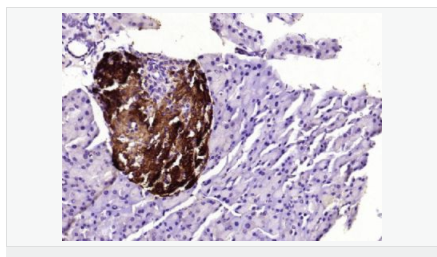

| 產品應用 | WB=1:500-2000 ELISA=1:5000-10000 IHC-P=1:100-500 IHC-F=1:100-500 ICC=1:100-500 IF=1:100-500 (石蠟切片需做抗原修復) not yet tested in other applications. optimal dilutions/concentrations should be determined by the end user. |